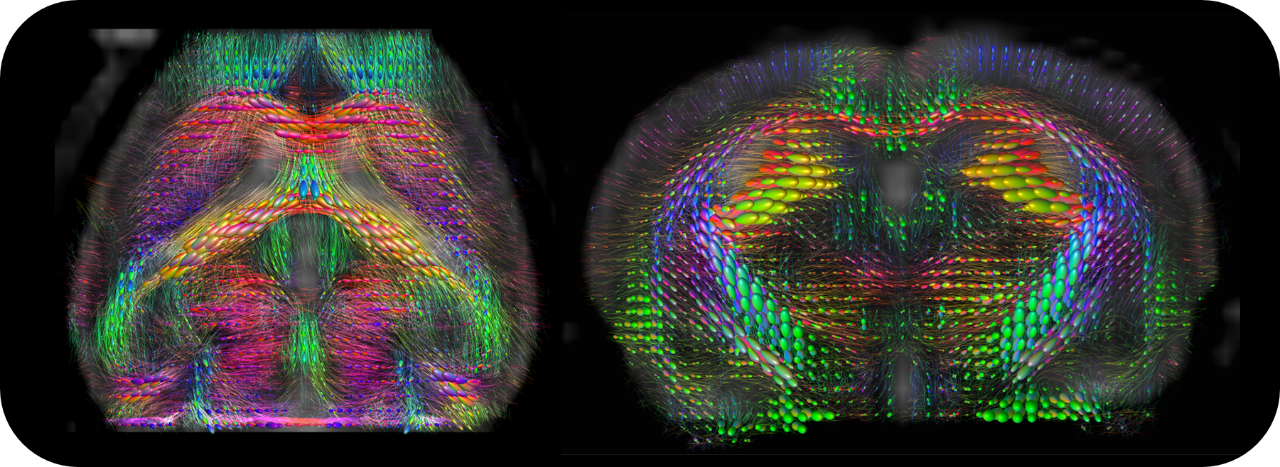

• MRI sequence portfolio of more than 1,000 sequence variations, including wireless cardiac imaging using navigator based IntraGate methods with cartesian or radial readout, as well as short echo time imaging, such as UTE and ZTE

Upgradable with state-of-the-art PET module as inline or insert with full field of view and accuracy offers real, homogeneous sub-millimetric volumetric PET resolution and quantification in all three axes, in the entire field of view. This is possible due continuous crystal detectors with SiPM technology and true depth of interaction 3D precision equivalent to 10+ layer pixelated crystal detectors.